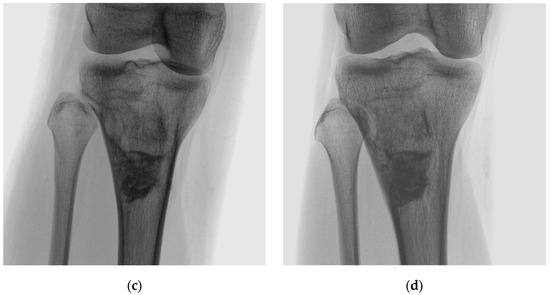

3 | 17 F | 1 | Right proximal tibia | 58 | Fibrous dysplasia | 22 |

9 | 27 F | 1 | Left tibial diaphysis | 41 | Fibrous dysplasia | 23 |